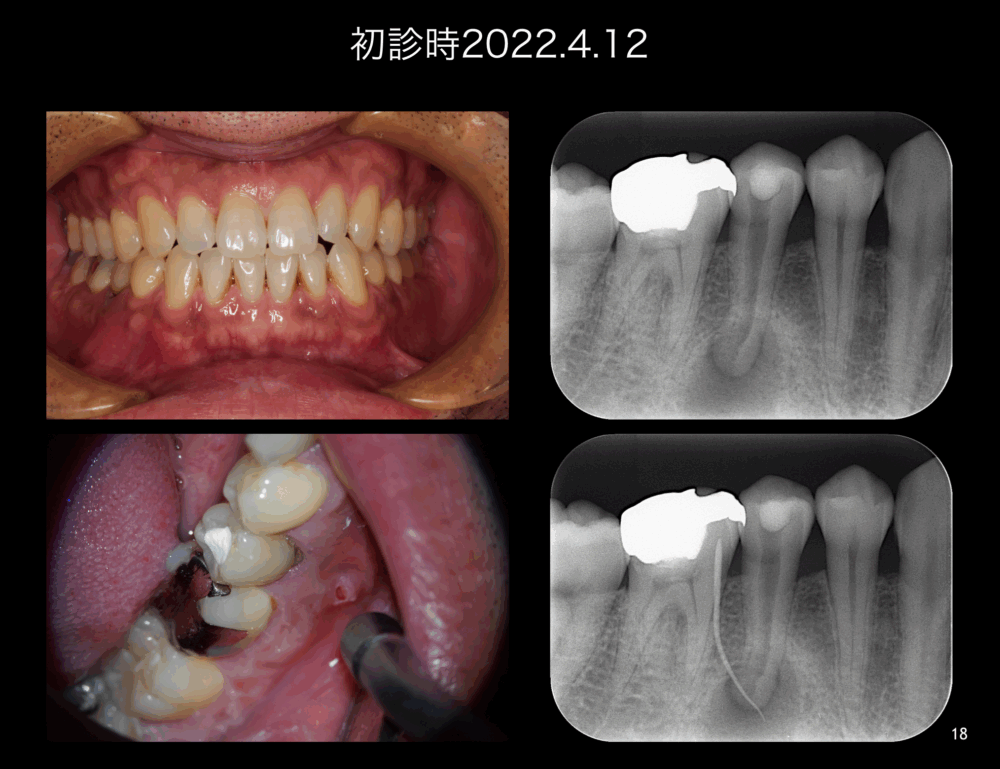

ももこ歯科のブログを読んでくださる皆さま、いつもありがとうございます。 前回は根管治療と歯根端切除術によりサイナストラクトが治癒したケースですが、 今回は根管治療と意図的再植術でサイナストラクトが治癒したケースです。 で...